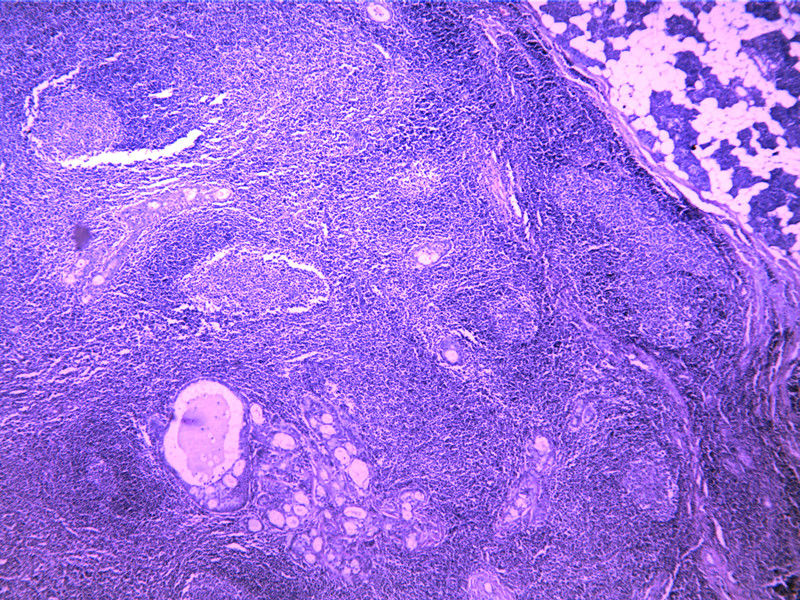

要想Hold住这个肿物的病理诊断,需要了解:

需要鉴别的肿瘤:

(1)皮脂腺淋巴腺瘤

(2)伴有淋巴组织间质的皮脂腺癌(皮脂腺淋巴腺癌)

(3)良性淋巴上皮病

(4)粘膜相关淋巴组织淋巴瘤(MALT淋巴瘤)

(5)转移性粘液表皮样癌